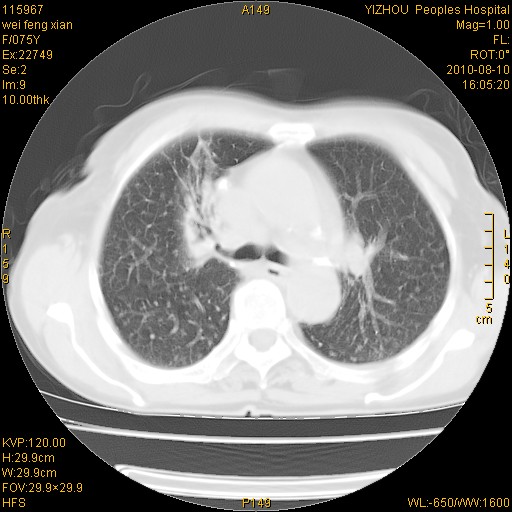

标题: CT28313:两肺弥漫性病变 [打印本页]

标题: CT28313:两肺弥漫性病变

女,75岁,患者反复头昏乏力面色苍白3年,再发10天入院。临床贫血查因。

双肺间质增生并右肺上叶炎性改变,不除外右肺上叶结核病肺内播散

考虑右肺上叶炎症合并双肺结核可能性大,建议上传纵隔窗ct图片。

双肺结核可能性大

考虑尘肺并结核;右上肺支气管扩张!

结核、尘肺、支气管肺泡癌都不能除外

右肺上叶继发性肺结核伴肺内血型播散!

考虑右肺上叶继发性肺结核伴两肺播散。